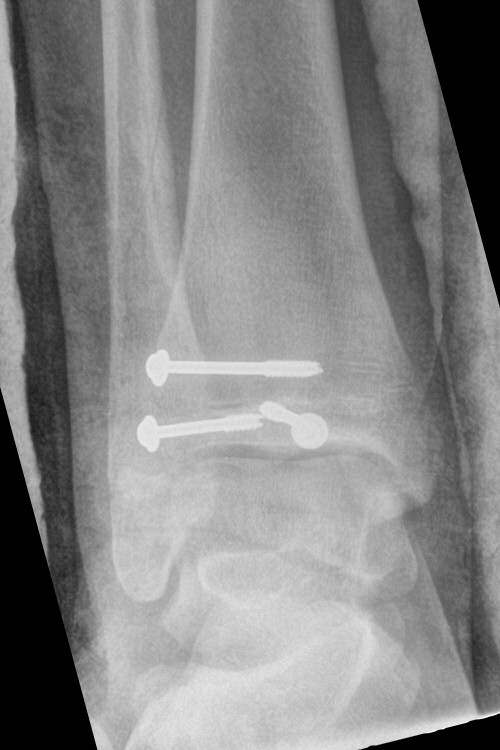

Exempel på triplansfraktur hos nästan färdigvuxet barn

Efter operation med skruvfixation

- Förbered för inläggning och snar operation, ofta med kanylerade skruvar. [2]